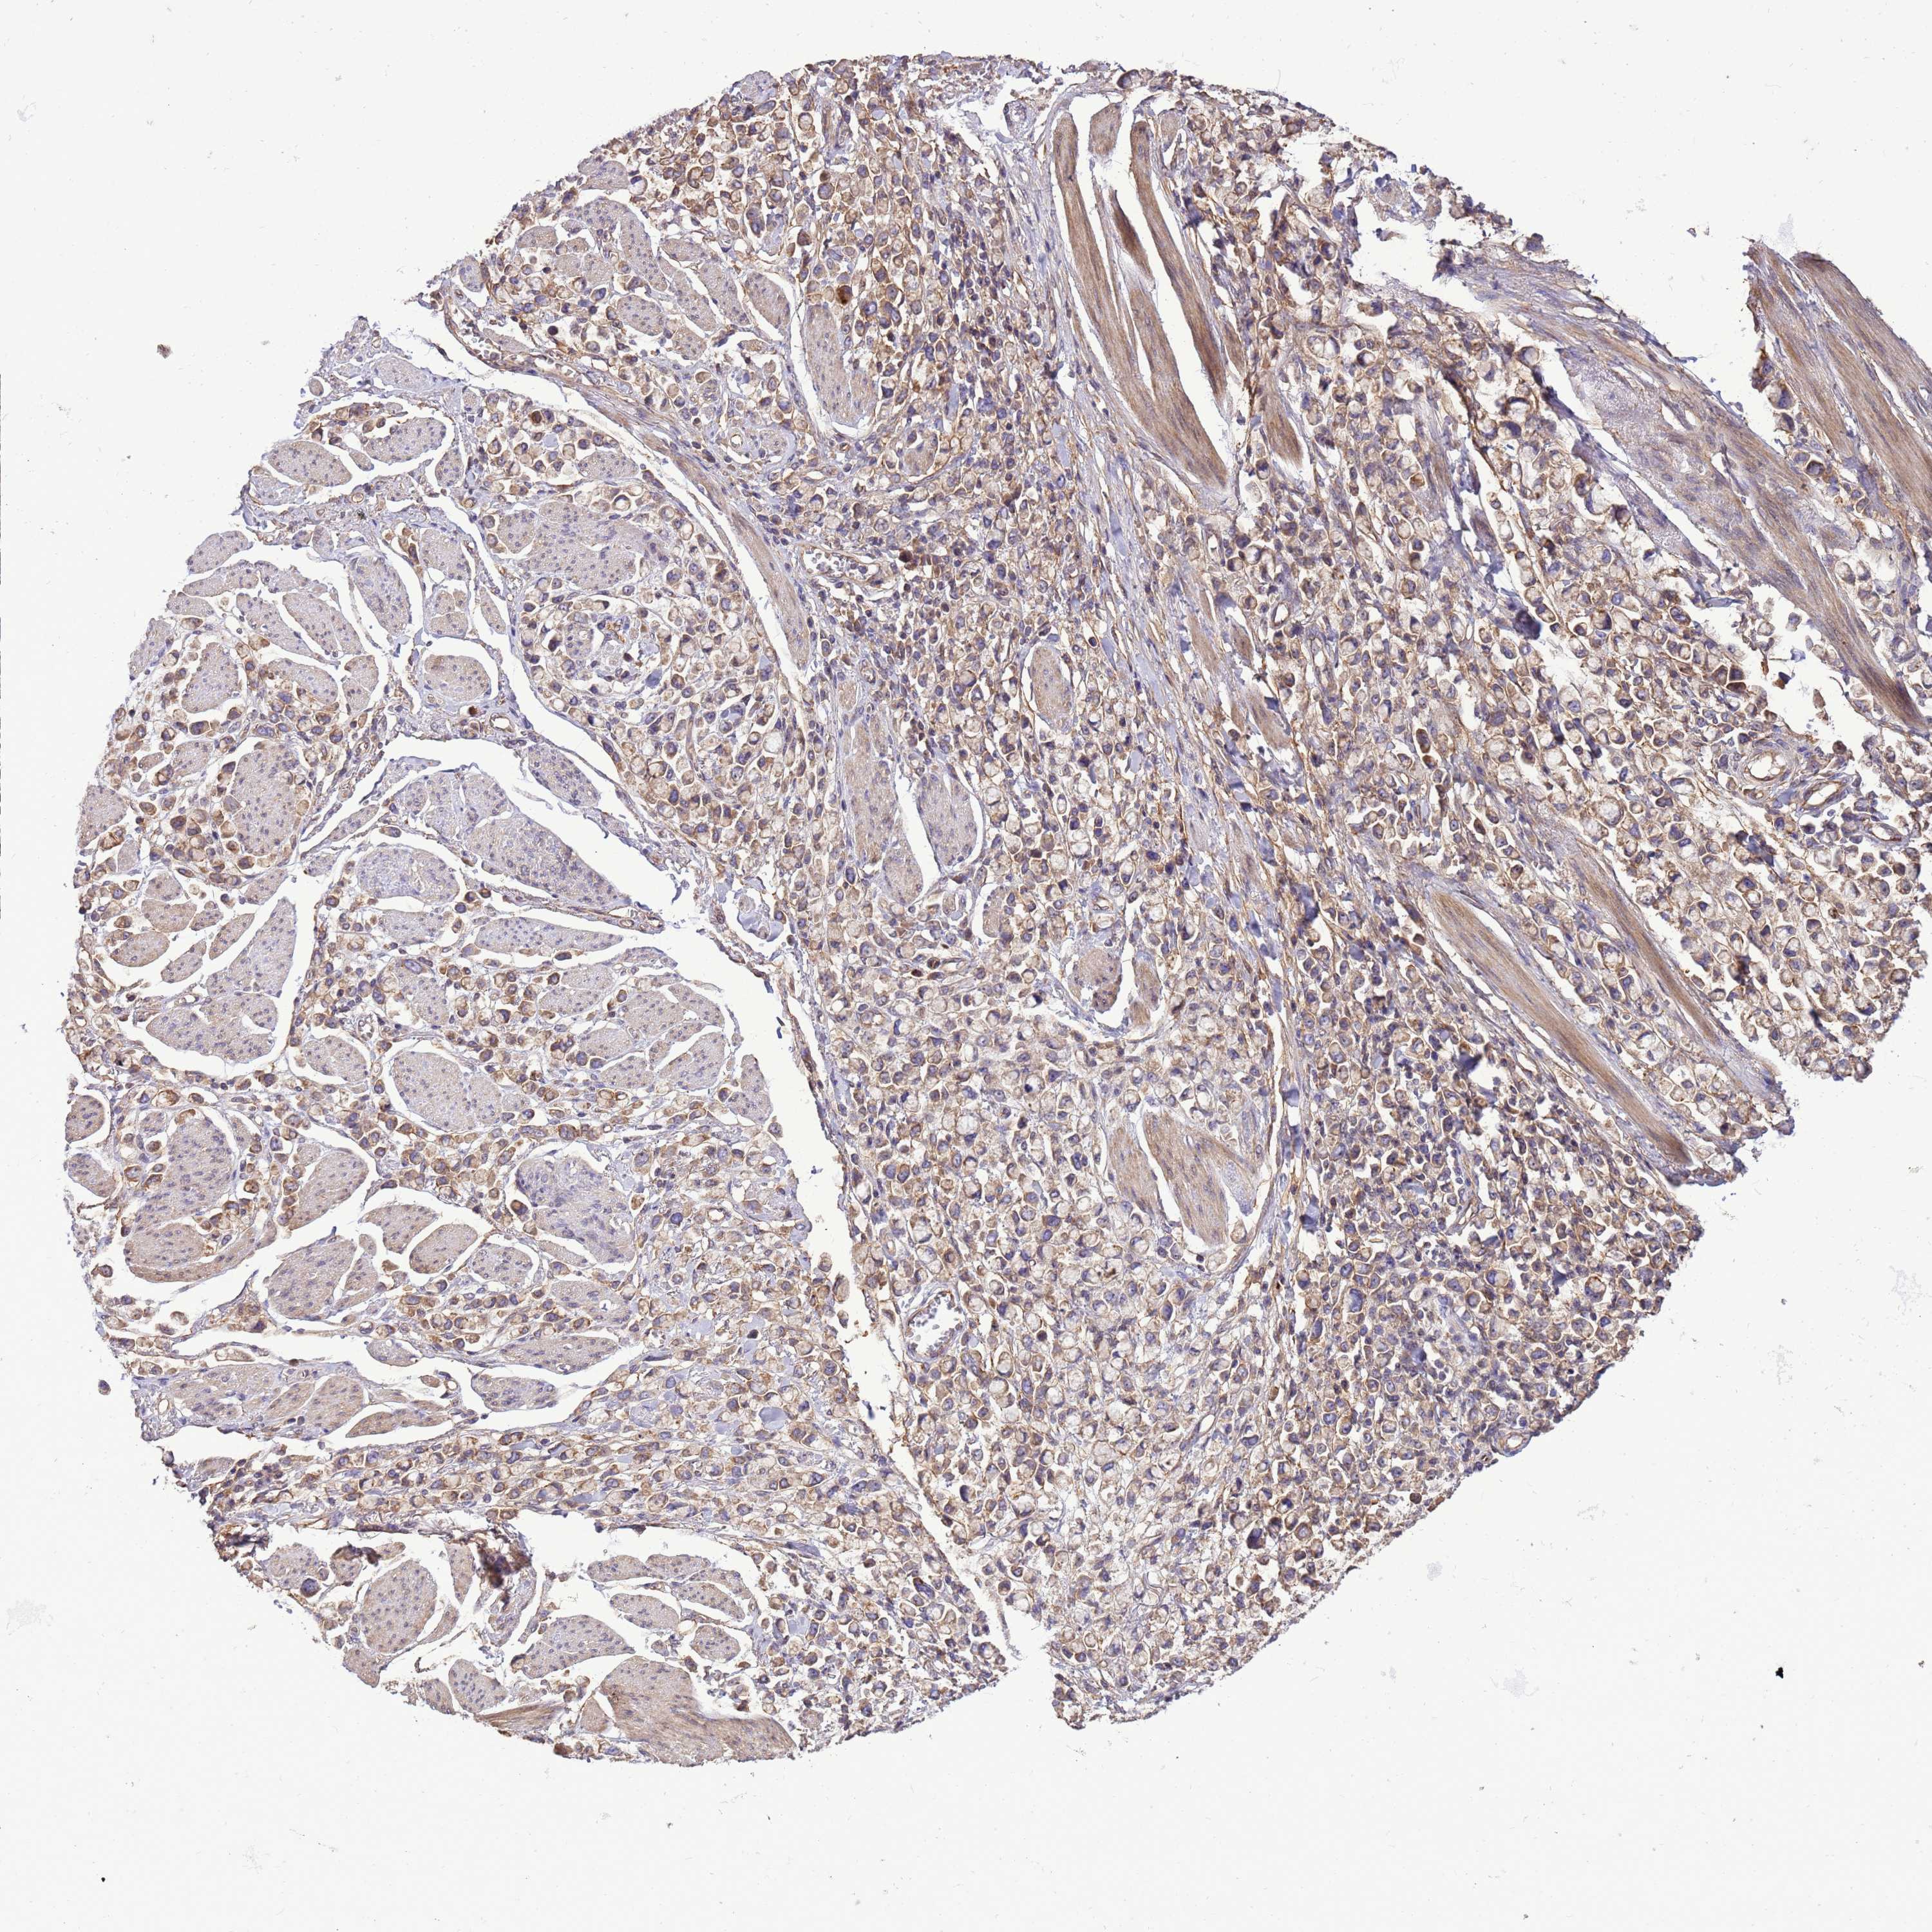

STOMACH CANCER - Protein expressioni

A mouse-over function shows sample information and annotation data. Click on an image to view it in a full screen mode. Samples can be filtered based on level of antibody staining by selecting one or several of the following categories: high, medium, low and not detected. The assay and annotation is described here.

Note that samples used for immunohistochemistry by the Human Protein Atlas do not correspond to samples in the TCGA dataset.

Antibody stainingi

Antibody staining in the annotated cell types in the current human tissue is reported as not detected, low, medium, or high, based on conventional immunohistochemistry profiling in selected tissues. This score is based on the combination of the staining intensity and fraction of stained cells.

Each image is clickable and will lead to virtual microscopy that enables deeper exploration of all samples and also displays staining intensity scores, fraction scores and subcellular localization as well as patient and tissue information for each sample.

Antibody HPA040574

Antibody HPA047804

Staining

High

Medium

Low

Not detected

Intensity

Strong

Moderate

Weak

Negative

Quantity

>75%

75%-25%

<25%

None

Location

Nuclear

Cytoplasmic/membranous

Cytoplasmic/membranous,nuclear

Adenocarcinoma, NOS

Adenocarcinoma, High grade